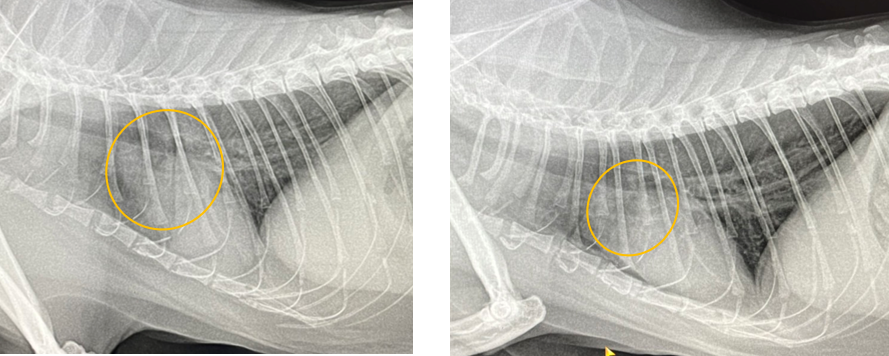

また、別のねこちゃんでは肺に水がたまってしまう肺水腫という状態になり、来院時は呼吸が苦しそうな状態でした。利尿剤というたまった水を出してあげるお薬を使い、呼吸の状態が落ち着いたため、今は飲み薬で通院していただいています。

左側の写真が利尿剤を使う前、右側が使った後の写真です。

心臓の周りの白くもやっとした部分がお薬を使った後に小さくなり、心臓の輪郭もはっきりしているのがわかるでしょうか。